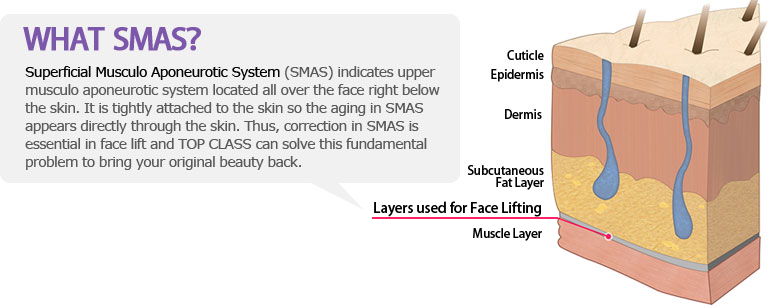

Wrinkle is the most obvious symptoms shown in the forehead. Deep forehead wrinkles developed from aging and repetitive use of muscles can make a person to look old and it even gives intimidating impression. Also loose skin on the forehead and the eyebrows can make the skin around the eyes loose. Thus, forehead lift surgery can improve both wrinkles and loose eyelids at the same time.

As people get older, skin gets looser that results in droopy eyelids

due to aging process.

Droopy eyelids can interfere with the vision and it can also make

a person look older by frowning.

Depending on how loose the skin is or individual condition, upper

eyelid lift, eyebrow lift, or lower eyelid lift can be carried out to solve

the problems with the eye area in middle age.

When a person ages, upper eyelid as well as lower eyelid sags and swells. Instead of simply removing such lower-eye fat, rearrangement of fat and strengthening of septum can be a better option for maintaining firmness and gives correctional effect as well.